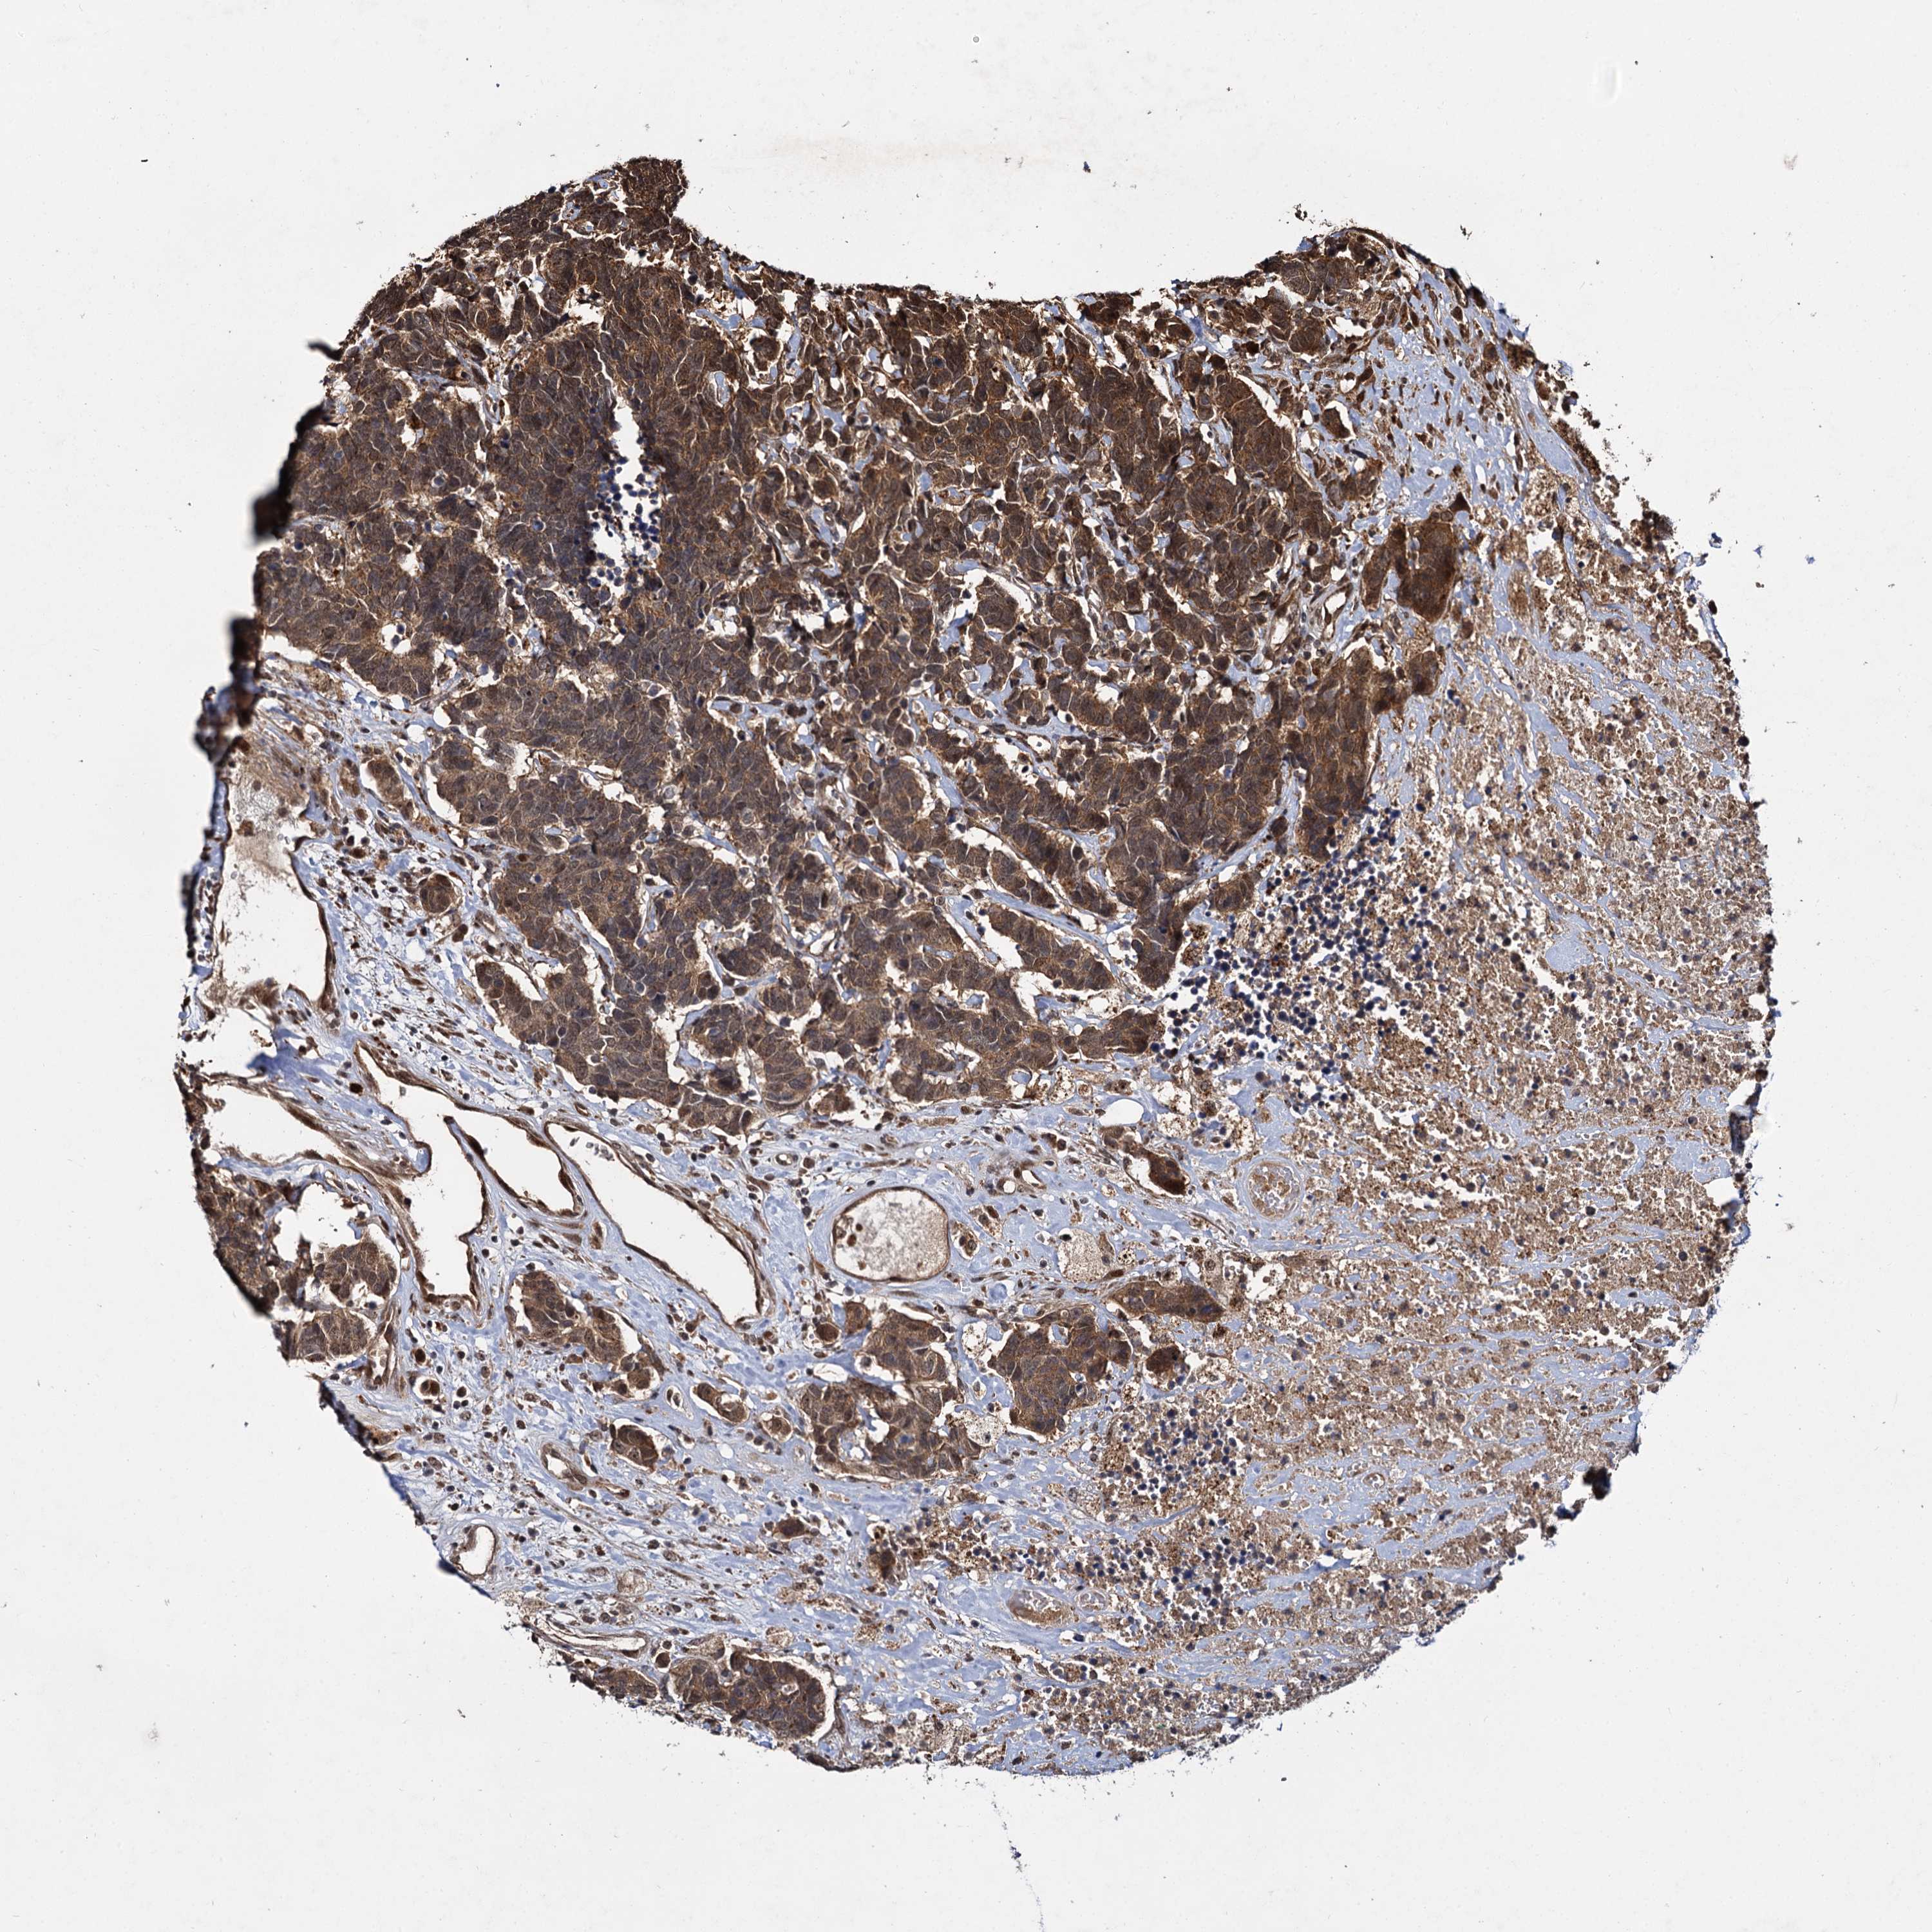

CARCINOID - Protein expressioni

A mouse-over function shows sample information and annotation data. Click on an image to view it in a full screen mode. Samples can be filtered based on level of antibody staining by selecting one or several of the following categories: high, medium, low and not detected. The assay and annotation is described here.

Antibody stainingi

Antibody staining in the annotated cell types in the current human tissue is reported as not detected, low, medium, or high, based on conventional immunohistochemistry profiling in selected tissues. This score is based on the combination of the staining intensity and fraction of stained cells.

Each image is clickable and will lead to virtual microscopy that enables deeper exploration of all samples and also displays staining intensity scores, fraction scores and subcellular localization as well as patient and tissue information for each sample.

Antibody HPA039392

Antibody HPA040503

Staining

High

Medium

Low

Not detected

Intensity

Strong

Moderate

Weak

Negative

Quantity

>75%

75%-25%

<25%

None

Location

Nuclear

Cytoplasmic/membranous

Cytoplasmic/membranous,nuclear

Carcinoid, malignant, NOS

Carcinoma, NOS